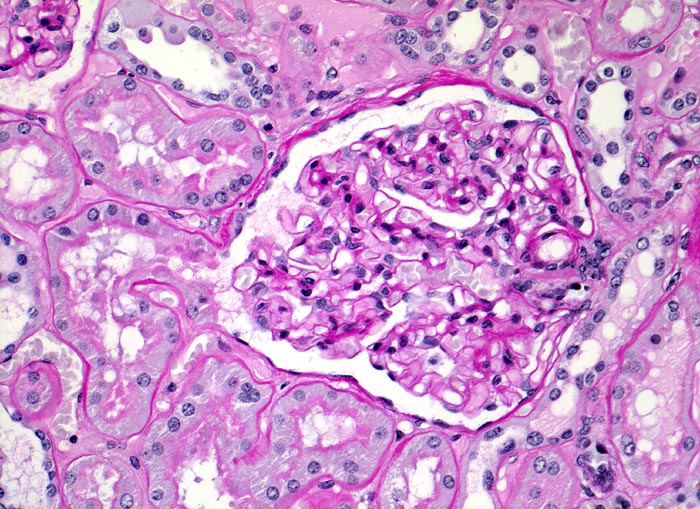

PathoPic ID 3443 - Normale Nierenrinde: Glomerulus mit Harnpol und Gefässpol.

Normale Nierenrinde: Glomerulus mit Harnpol und Gefässpol.

Unauffälliger Glomerulus mit

Harnpol (Hauptstück des proximalen Konvoluts) und

Gefässpol. Zarte glomeruläre Basalmembranen und normozelluläres Mesangium. Entzündungsfreier tubulointerstitieller Raum. Zarte tubuläre Basalmembranen.

Histologie

200